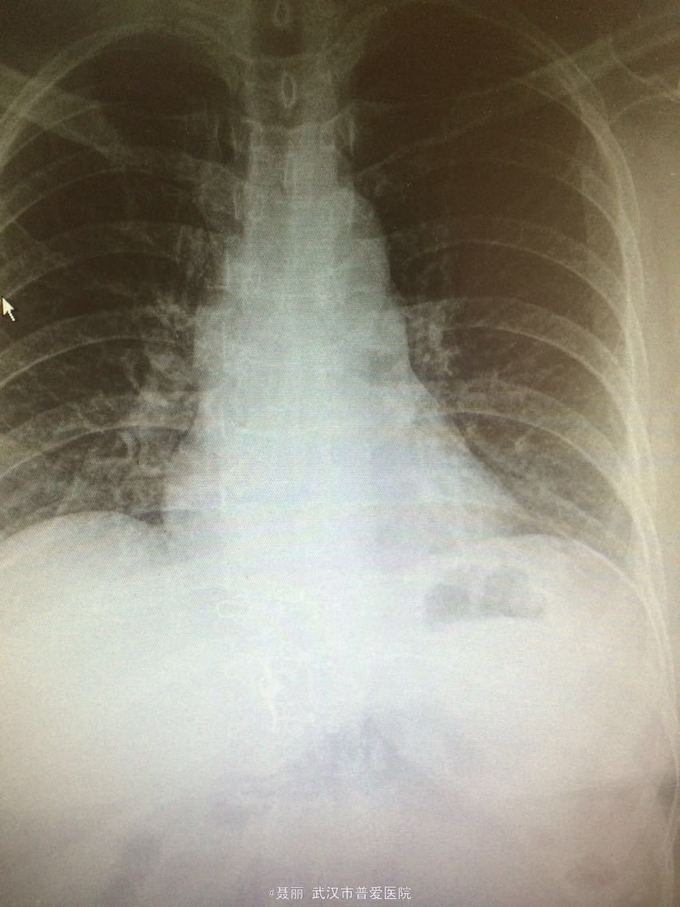

初步诊断:腰椎滑脱症 治疗计划:1、完善相关检查:胸片、心电图,血常规,尿常规,肝肾功能电解质、术前全套 2,活血化瘀扩管治疗。卧床休息。 L4滑脱复位+L4/5椎间盘摘除、椎管减压+椎间cage3植骨融合术